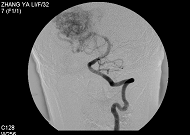

1.選擇性腸道血管造影1960年以來選擇性或高選擇性血管造影是診斷本病的主要手段,其診斷率可達75%~90%。血管造影中血管畸形可分為3型:Ⅰ型為動-靜脈吻合或黏膜下血管發育不良;Ⅱ型為血管錯構瘤;Ⅲ型為出血性毛細血管擴張症(如系遺傳因素所致,則稱為遺傳性出血性毛細血管擴張症,也稱Osler-Weber-Rendu綜合徵)。血管造影后的主要徵象有:

(1)異常增多的血管叢,結構紊亂。

(2)末梢血管蜘蛛狀擴張及迂曲。

腸道血管畸形造影圖(4)出血期可見造影劑外溢積聚在腸腔內。

(5)靜脈期顯示腸系膜緣一側的腸壁內靜脈擴張、迂曲。